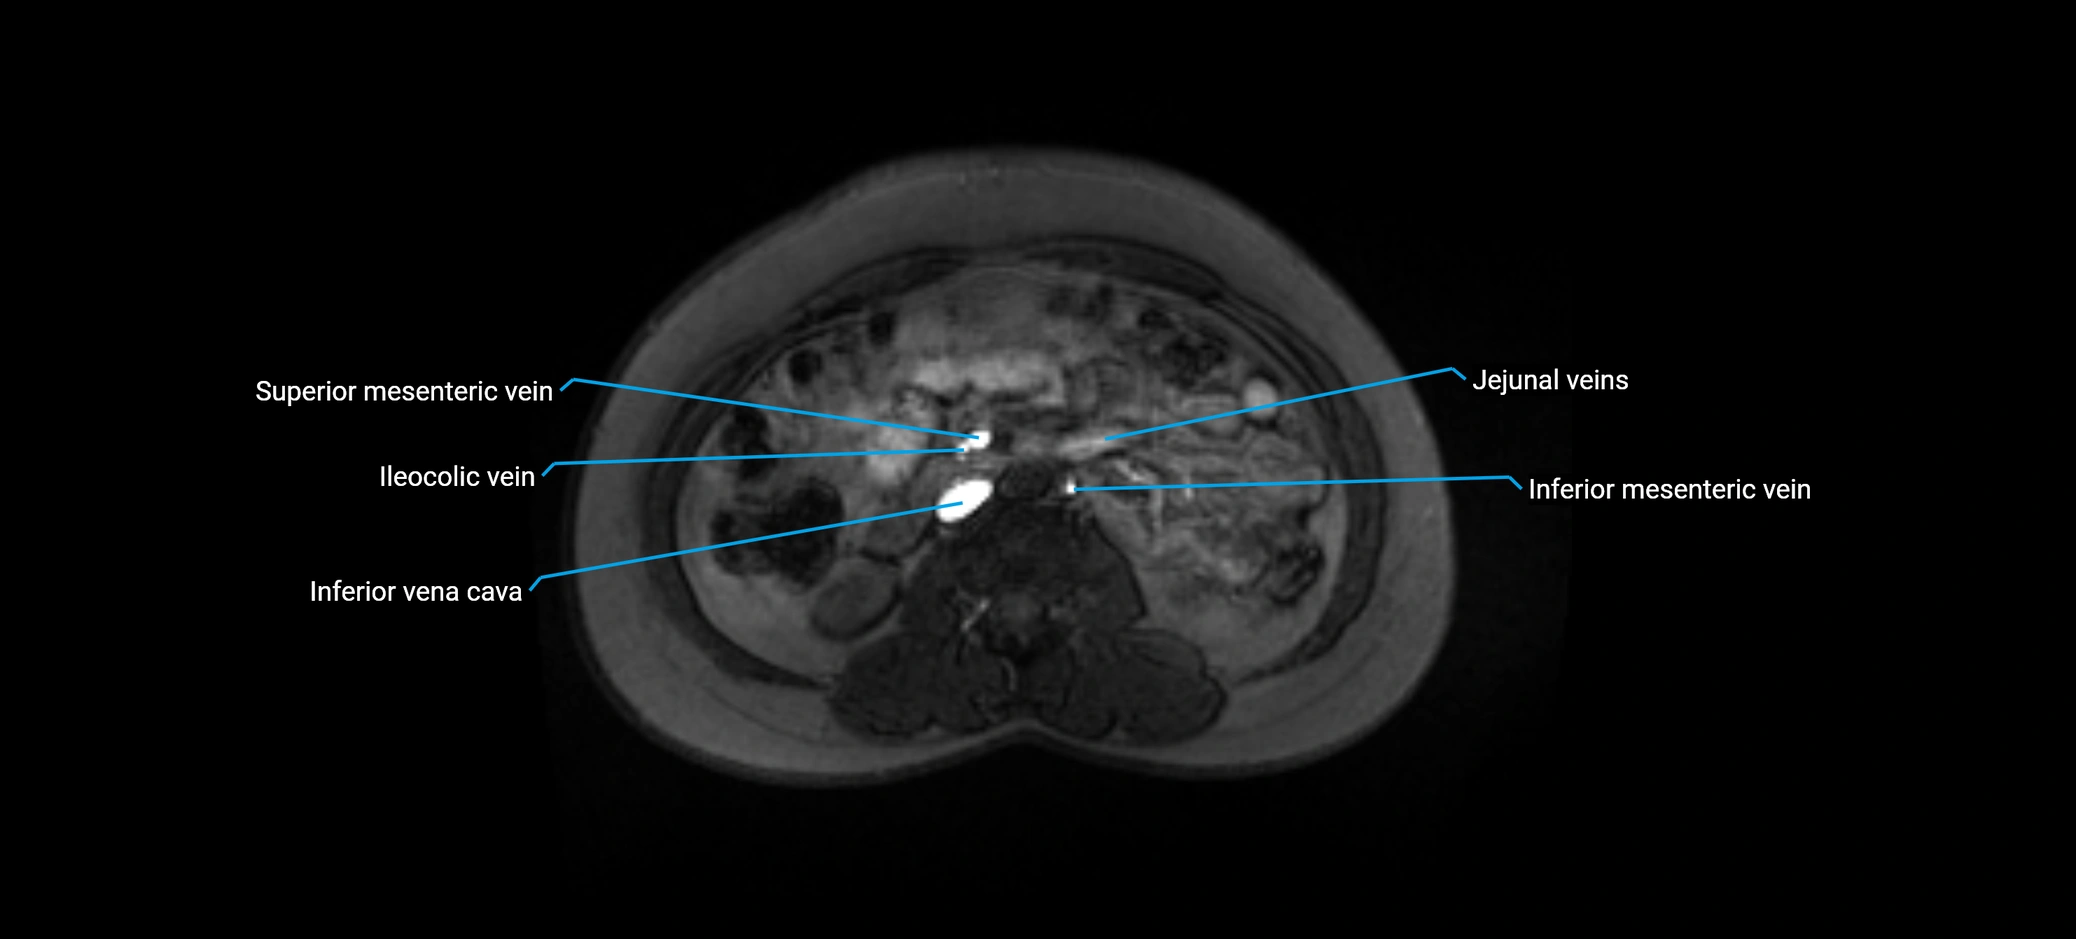

MRI image

image